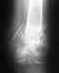

в возросте 6-ти лет была травма локтевого сустава из записей в карте:30.7.1986г. девочка упала 4.7.1986г ударилась левым локтевым суставом отечность и боль сохранялись.при осмотре: сустав деформирован движения ограничены.Рен-ма -перелом внутреннего надмыщелка с большим смещением.направлена в травмотологическое отд.больше никаких записей не нашла...насколько помню была сделана операция ,стояла спица...после снимок не делали.от физ.нагрузок была освобождена (только ЛФК)рука болела ,вверх поднимать больно было всегда.доктора списывали на то ,что она травмирована.в 2010 году появилось ощущение слабости,онемения мизинца и ощущения покалывания,и будто в суставе что-то мешает боли стали частыми,рука выглядит худее правой.Обратилась к ортопеду,диагноз- ложный сустав внутреннего мыщелка левого локтевого сустава ,неврит локтевого нерва.было назначено консервативное лечение ,которое не помогло .31.03.2011-клинический диагноз основной: ложный сустав внутреннего надмыщелка левого плеча,туннельный синдром.Компрессионная невропатия локтевого нерва. Проведенное лечение:декомпрессия левого локтевого нерва..первые 4 дня исчезли ощущения онемения,боли и покалывания в 5 и части 4го пальцев ...но как только начала движение в локтевом суставе - ощущения вернулись...боль в суставе усилилась.болит вся ладонь ,запястье,большой палец,руку не могу держать вверх(причесаться,вымыть посуду и много других действий приченяет боль),спать не могу ,к вечеру и после движений облась локтевого сустава горячее.это теперь постоянное состояние или что то можно сделать?

• Кликните для загрузки файла 0123.JPG